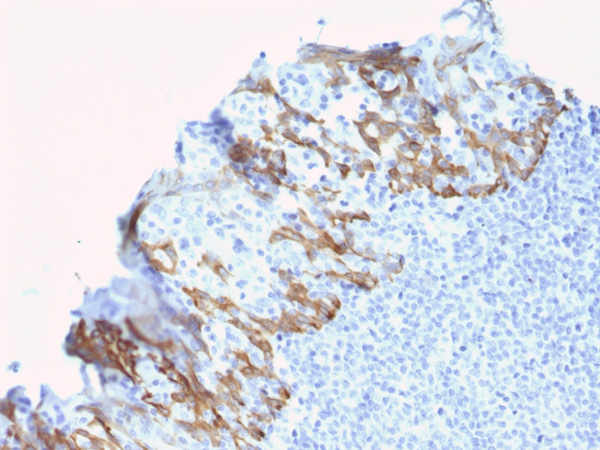

IHC (Immunohistochemisry)

(Formalin-fixed, paraffin-embedded human Breast Carcinoma stained with ZNF690/ZSCAN29 Mouse Monoclonal Antibody (ZSCAN29/2610).)